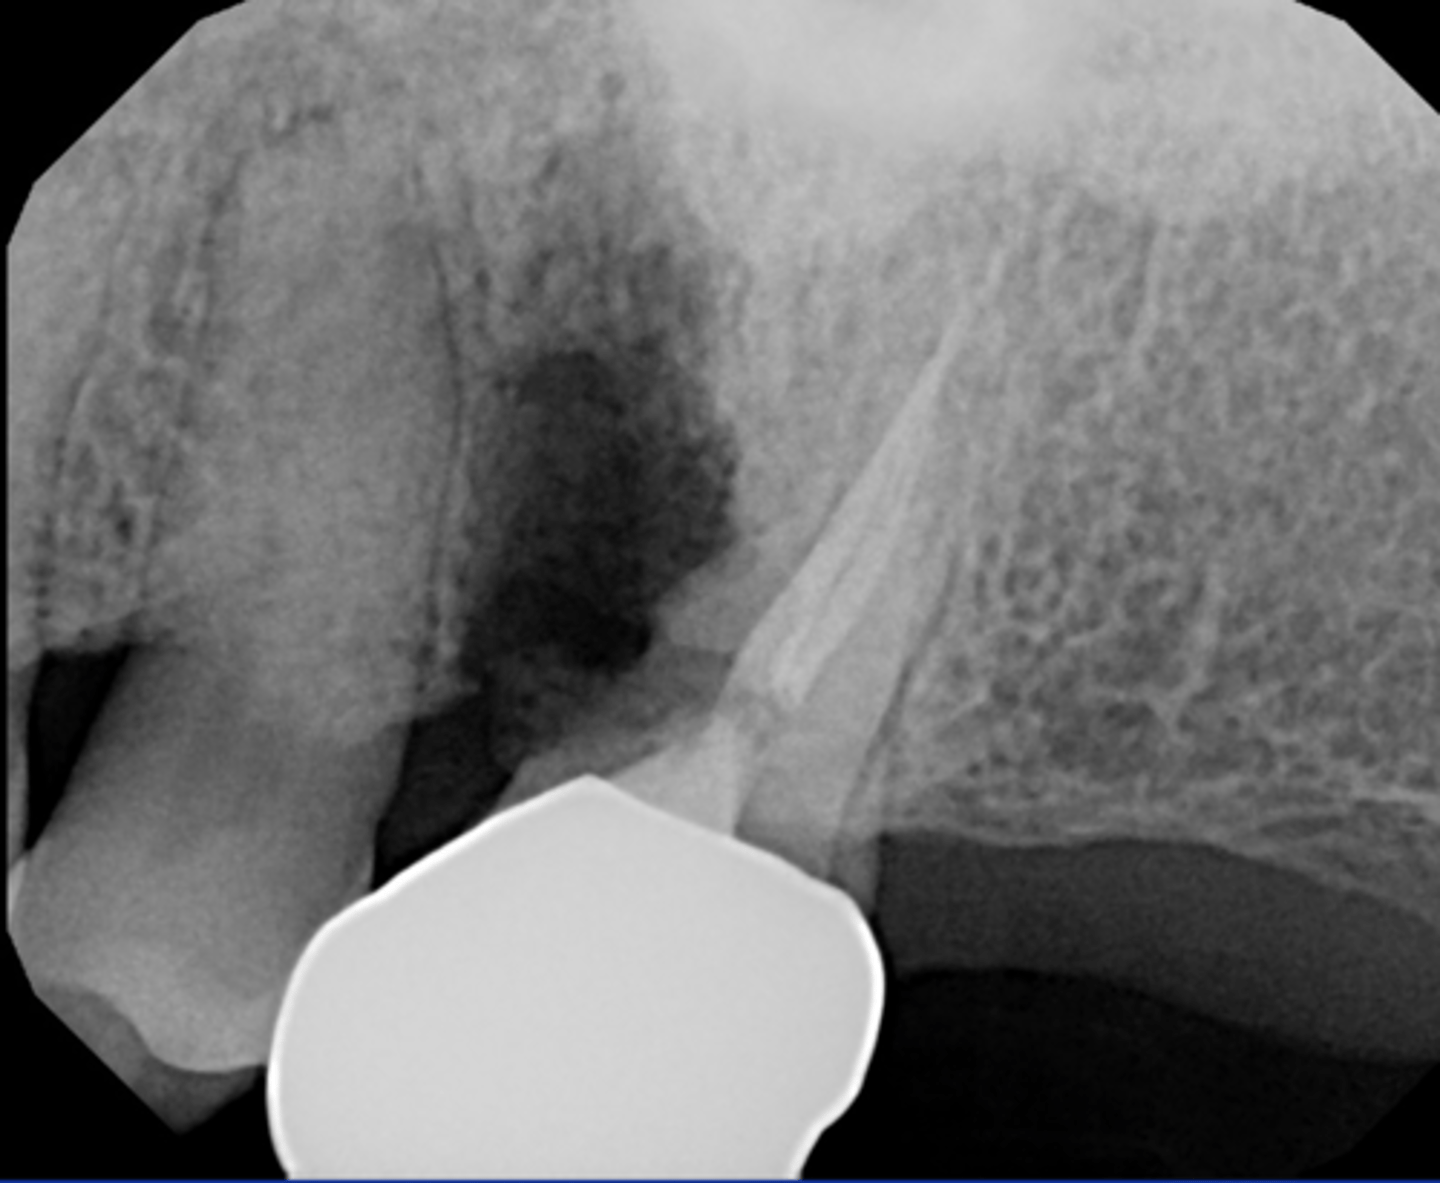

Check if missed MB2

RCT 10 years ago thru bridge

Sinus tract 3 years ago...apicoectomy done

Sinus tract returned.

What do we do?